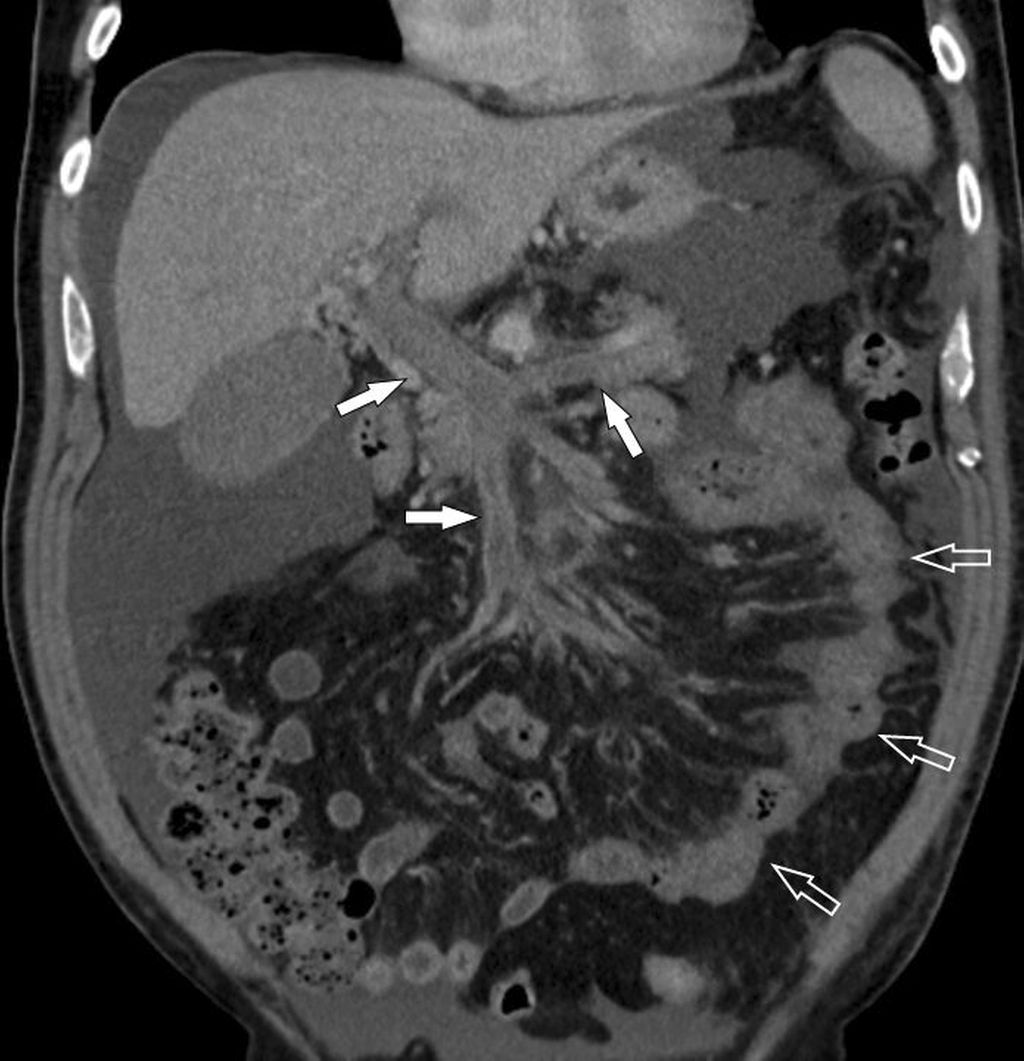

Abb. 6: Pfortader- und Mesenterialvenenthrombose: Die MDCT zeigt die ausgedehnte Thrombose (Pfeile oben) und den ischämischen, wandverdickten Dünndarm (offene Pfeile). In der Laparotomie fand sich eine Dünndarmnekrose

Die am meisten gefürchtete Komplikation bei Ausdehnung der PVT in die Mesenterialvenen ist das Auftreten einer hämorrhagischen Dünndarminfarzierung (Dünndarmnekrose) mit hoher Morbidität und Letalität (Abb. 6). Insgesamt sind bei Verdacht auf das Vorliegen einer Pfortaderthrombose die frühe bildgebende Diagnostik mittels farbcodierter Duplexsonografie und bei inkonklusiver Sonografie eine Kontrastmittel-verstärkte MDCT wichtig für das weitere therapeutische Management.